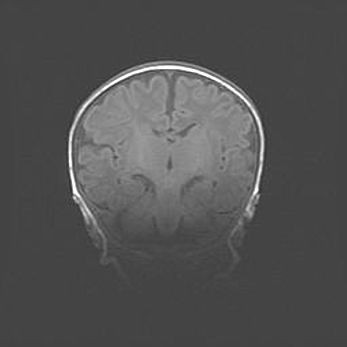

Открытая гидроцефалия.

Возраст: 9 месяцев 12 дней

Вес: 6800 г

Пол: мужской

Окружность головы: 41,5 см

Срок гестации: 28 недель

Гидроцефалия головного мозга у новорожденных имеет характерный признак: опережающий рост окружности головы приводит к визуально хорошо определяемой гидроцефальной форме сильно увеличенного в объёме черепа. Детские неврологи определяют следующие симптомы гидроцефалии у грудничков: выбухающий напряжённый родничок, частое запрокидывание головы, смещение глазных яблок к низу.